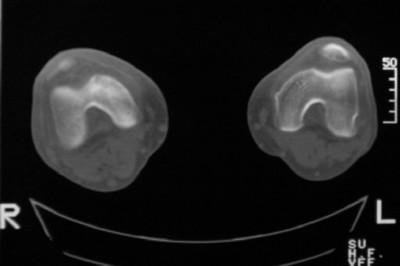

标题: CT8024:会诊!!!男 60 岁 双漆关节疼痛半年,进行性加重 [打印本页]

患者男 60 岁 双漆关节疼痛半年,进行性加重.

右股骨内髁关节面下多个不规则小囊变,边缘有明显硬化边,.......考虑: 1.关节面下骨囊变.  2.类风湿关节炎?   3.血友病?

右侧髁间隆突变尖,软骨下假囊肿形成,结合病人年龄较大,首先考虑退行性骨关节病。关节周围软组织未见明显异常,病人单单一双膝关节出现症状,不太支持类风湿性关节炎,可结合化验室检查。